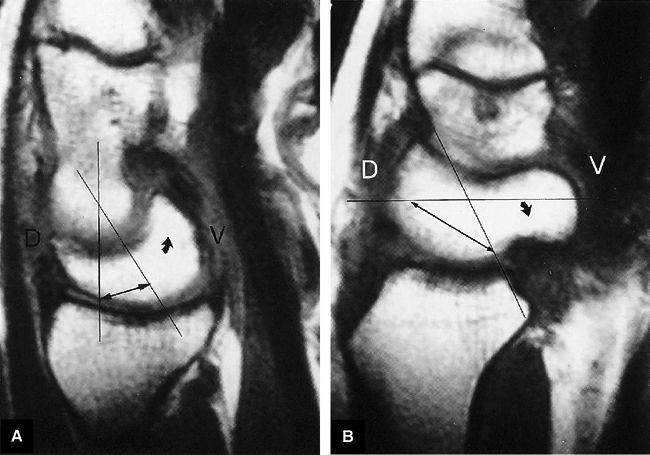

FIGURE 10.89 ● (A) DISI with dorsal tilting of the lunate (curved arrow) without volar shift. Note the dorsal displacement of the capitate relative to the radius. The capitolunate angle (double-headed arrow) measures 32°. (B) Palmar tilting of the scaphoid (curved arrow) causes an abnormally increased scapholunate angle (double-headed arrow) of 124°. D, dorsal; V, volar.

FIGURE 10.90 ● Scapholunate ligament tear with DISI. (A) Traumatic avulsion of the lunate aspect of the scapholunate ligament on a fast STIR coronal image. The scapholunate interval is widened with direct extension of fluid filling the tear site (large straight arrow). Ligament fibers are still attached to the radial aspect of the lunate (small straight arrow). Morphology is amorphous at the avulsed scaphoid remnant (curved arrow). (B) The capitolunate angle (arrow) is increased to 46°, and there is associated dorsal tilting of the lunate. (C) The scaphoid tilts palmarly with an increased scapholunate angle (arrow) of 142°.